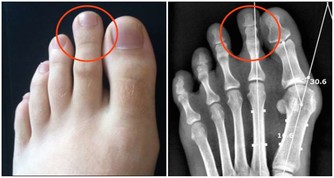

1、血液黏稠度在各種血型中,最容易升高。(健康隱患:腦梗塞)

2、血小板黏附率明顯高出正常對照組。(健康隱患:偏頭痛)

3、末梢血管調節功能差,對冷刺激比較敏感。(健康隱患:凍瘡)